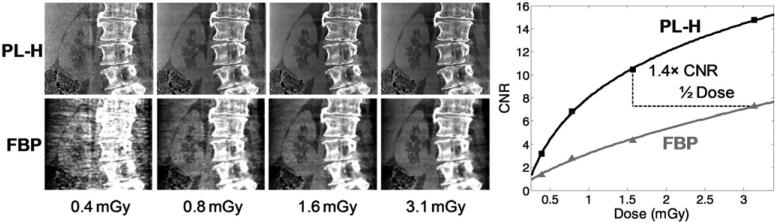

Because the lowest-contrast sphere available in the phantom had a slightly higher absolute contrast (~80 HU) than the sphere in the head, a higher value of δ = 5 HU was used for the Huber penalty, and the matched spatial resolution comparison was conducted at a slightly higher spatial resolution of σ = 1.0 mm, where substantial gain in CNR could still be achieved at higher spatial resolution. At such matched spatial resolution, the CNR for PL-H and FBP are shown in figure 8, with PL-H demonstrating that 50% dose reduction can be achieved while maintaining an increase in CNR (by 2.2 × ). Although scatter and beam-hardening contribute to artifacts in both the PL-H and FBP images, the difference in shading across the images is likely due to the different truncation correction methods applied—specifically, an elliptic object support for PL and zero-order extrapolation of the projection data at the edges for FBP. While not the focus of this paper, future work will seek to implement better correction methods and quantify their impact on artifact reduction.

Figure 8.

Image quality comparison at matched spatial resolution (σ = 1.0 mm) for CBCT of the abdomen phantom. PL-H maintains a CNR advantage over FBP—for example, increasing CNR by a factor of 2.2 at 1.6 mGy (0.94 mA × 64 s × 0.026 mGy/mAs) in comparison to FBP at 3.1 mGy. Images are displayed with a grayscale window of [0.015, 0.025] mm–1.

3.3. Cadaveric torso

Because the spatial resolution in the cadaver images could not be easily quantified and verified as in the phantom studies above, the PL-H and FBP reconstruction parameters that generated a matched spatial resolution of σ = 1 mm for the 80 HU contrast sphere in the abdomen phantom were applied to the cadaveric torso. A fair comparison between PL-H and FBP is still expected due to the similarity in size and low-contrast imaging task as well as the identical scanning protocols between the cadaver and abdomen phantom. The fresh cadaver provides realistic soft-tissue imaging with kidney to fat contrast of ~120 HU, which is slightly higher than the sphere considered in the abdomen phantom. The ellipse-fitting initialization method yielded a reconstruction FOV of 30.0 × 21.0 × 18.0 cm3, with 18.0 cm of longitudinal coverage sufficient to prevent longitudinal truncation of any projection ray within the volume.

Continuing the focus on soft-tissue imaging, CNR was calculated in the cadaver abdomen using the contrast between the right kidney and surrounding fat, while noise was measured in the somewhat homogeneous liver after subtraction with a high-quality (12.5 mGy) reference image reconstructed with the respective PL-H and FBP algorithms. As shown in figure 11, PL-H once again boosts the CNR relative to FBP, validating the results shown above for the anthropomorphic phantoms. Furthermore, in addition to the improved soft-tissue visualization at approximately matched spatial resolution for soft-tissue, it is easy to appreciate that the Huber penalty preserves the sharpness of high-contrast structures such as the spine and air/tissue interfaces, which for FBP are uniformly smoothed along with the soft-tissue.

Figure 11.

C-arm CBCT images of the cadaver at the same dose levels and reconstruction parameters for σ = 1.0 mm as used in the anthropomorphic abdomen phantom. The results validate a major improvement in image quality (and/or capability for dose reduction) with PL-H. Display window [0.015, 0.025] mm–1.

The cadaver images also validate the previous results regarding sparse sampling. In particular, the qualitative image appearance and quantitative CNR metric confirm the advantage of sparse sampling at ultra-low dose, as well as the advantage of remaining fully sampled at higher dose, with a crossover at ~1.7 mGy (for simplicity, only the PL-H comparison is shown in figure 12). The crossing point in dose level is slightly higher in the cadaver than the phantom and is possibly attributable to different amounts of the object-specific streak artifacts and potentially inexact matching of spatial resolution after duplicating reconstruction parameters from the phantom to the cadaver, especially in the cases of sparse sampling. Nonetheless, the overall dose regimes appropriate for the fully sampled and half-sampled cases is clear, while the quarter-sampled reconstructions have poor recovery of soft-tissue features.

Figure 12.

Sparse sampling comparison in the cadaver. At low dose levels (below ~ 1.7 mGy in this case), 50% sparsity yields the best image quality, while at higher dose levels, image quality is best when fully sampled. Soft-tissue structures can be difficult to recover when there are too few samples (25% sparsity), regardless of dose level.